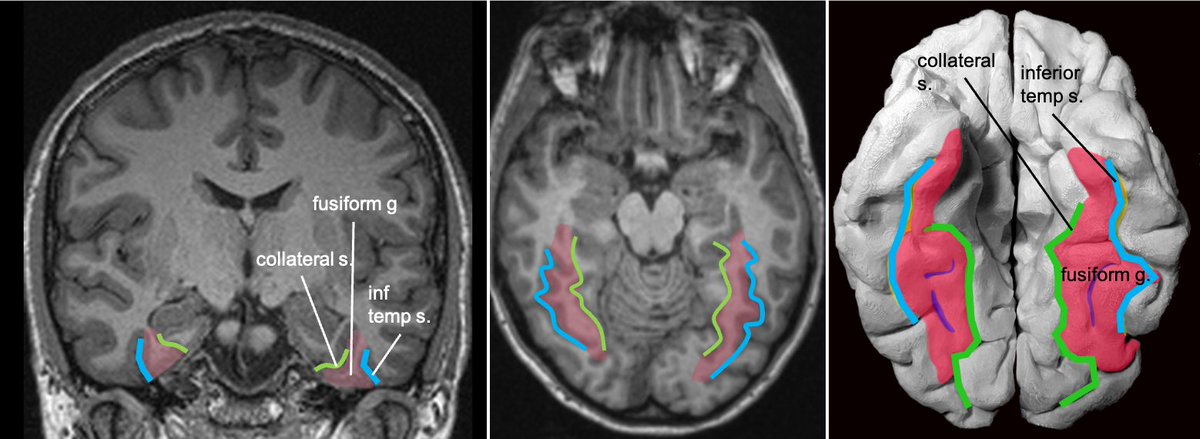

Gyral anatomy of inf occipitotemporal surface: The inf. temp. gyrus wraps from lateral https://abs.twimg.com/emoji/v2/... draggable="false" alt="➡️" title="Pfeil nach rechts" aria-label="Emoji: Pfeil nach rechts">inferior. The fusiform and lingual gyri span from occipital lobe posteriorly to temporal lobe anteriorly. Parahippocampal is medial temporal (anterior continuation of the lingual g).

https://abs.twimg.com/emoji/v2/... draggable="false" alt="➡️" title="Pfeil nach rechts" aria-label="Emoji: Pfeil nach rechts">inferior. The fusiform and lingual gyri span from occipital lobe posteriorly to temporal lobe anteriorly. Parahippocampal is medial temporal (anterior continuation of the lingual g).

Fusiform g is just lateral to lingual g on the inf surface of temporal lobe, separated by collateral sulcus. It& #39;s medial to the ITG, separated by ITS. Involved in face and body recognition; word form recognition (on left). (Fusiform g was not definitively involved by tumor). 9/13

inferior. The fusiform and lingual gyri span from occipital lobe posteriorly to temporal lobe anteriorly. Parahippocampal is medial temporal (anterior continuation of the lingual g).6/13" title="Gyral anatomy of inf occipitotemporal surface: The inf. temp. gyrus wraps from lateralhttps://abs.twimg.com/emoji/v2/... draggable="false" alt="➡️" title="Pfeil nach rechts" aria-label="Emoji: Pfeil nach rechts">inferior. The fusiform and lingual gyri span from occipital lobe posteriorly to temporal lobe anteriorly. Parahippocampal is medial temporal (anterior continuation of the lingual g).6/13" class="img-responsive" style="max-width:100%;"/>

inferior. The fusiform and lingual gyri span from occipital lobe posteriorly to temporal lobe anteriorly. Parahippocampal is medial temporal (anterior continuation of the lingual g).6/13" title="Gyral anatomy of inf occipitotemporal surface: The inf. temp. gyrus wraps from lateralhttps://abs.twimg.com/emoji/v2/... draggable="false" alt="➡️" title="Pfeil nach rechts" aria-label="Emoji: Pfeil nach rechts">inferior. The fusiform and lingual gyri span from occipital lobe posteriorly to temporal lobe anteriorly. Parahippocampal is medial temporal (anterior continuation of the lingual g).6/13" class="img-responsive" style="max-width:100%;"/>